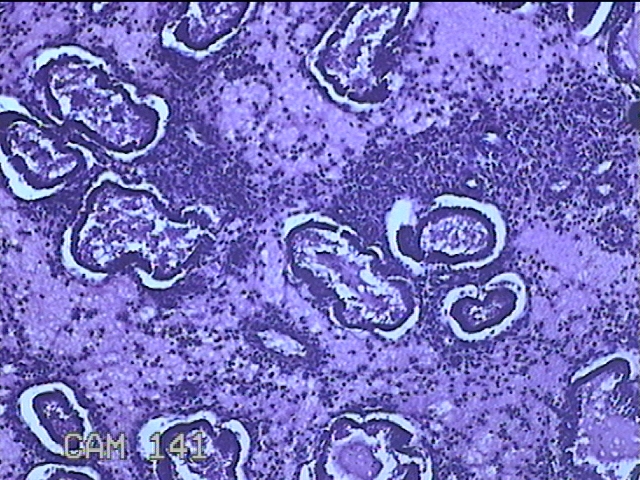

性别

女

年龄

41岁

临床诊断

异常子宫出血;取出子宫内节育器;子宫内膜炎

一般病史

阴道不规则流血2个月。

标本名称

宫腔内容物

大体所见

灰白暗红色不规则碎组织3.5x2.5x0.8cm一堆。